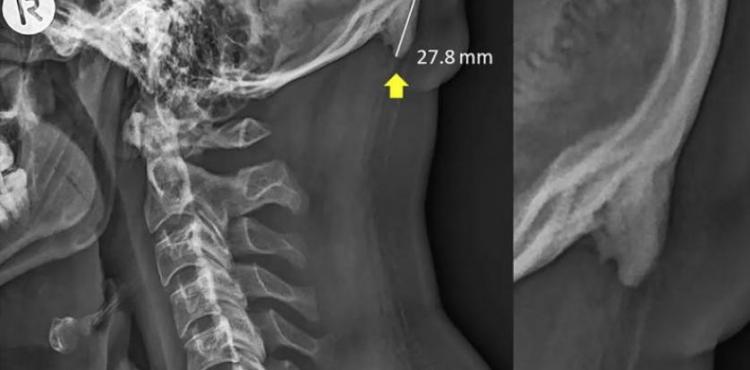

كثرة استخدام الجوالات تتسبب بإخراج "قرون" !